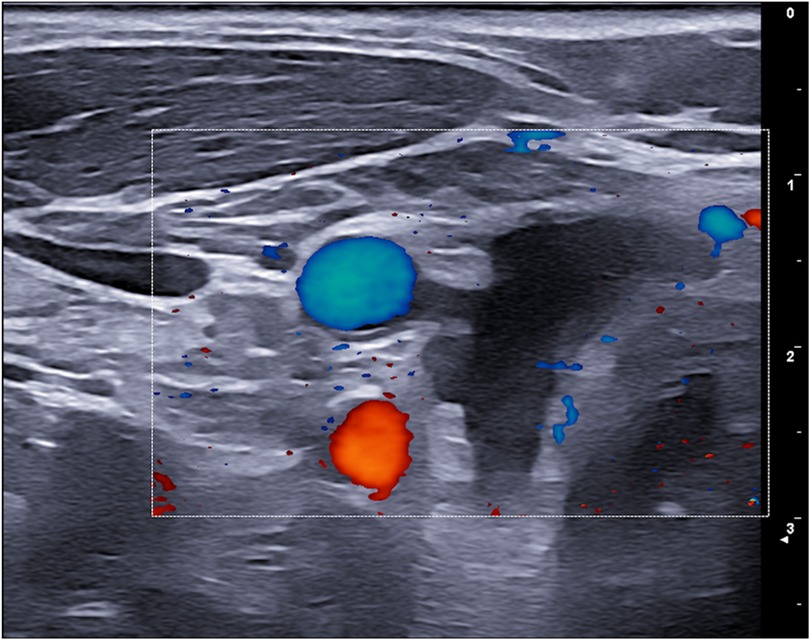

Figure 4

Ultrasound image showing a cross-sectional view with color Doppler mapping. Two distinct colored areas are visible: a blue circular area at the top and a red irregular-shaped area at the bottom, indicating blood flow direction and speed. Grayscale layers indicate tissue structures.

Figure 4. 6-month ultrasound follow-up with no recurrence of cysts or cystic degeneration.